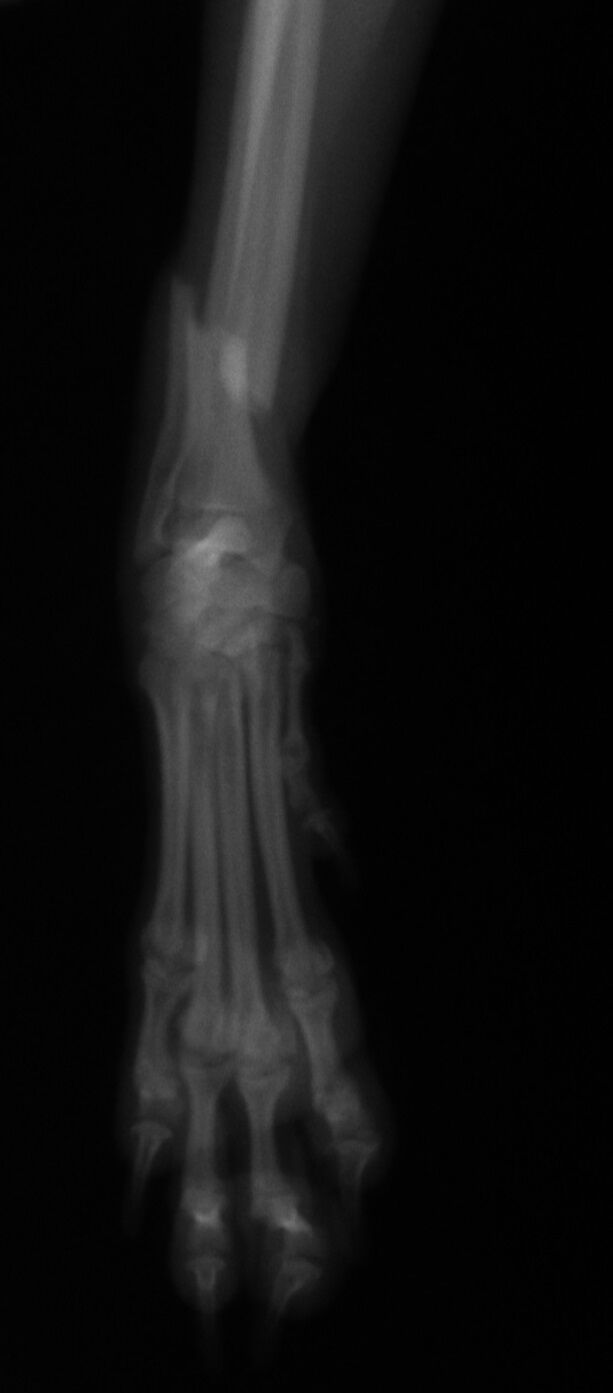

手術後1か月は外固定で補助します。その後、レントゲンで問題ないことを確認し外固定を外しました。外した後は普通に歩行し、散歩なども普段通りにしてもらいます。獣医師によってはプレートを残したままにすることがありますが、中にはプレート部分の骨が細くなってしまうことがあります。もし仮にプレートが折れてしまった時には大変な手術が必要になることがあります。当院では高齢犬であればプレートを残したままにするのですが、この症例は若かったので上記の心配もありますので、プレートを除去することにしました。ただトイ・プードルは骨の増生が良くないことが多いので、プレートを外した直後に再骨折したということがよくあります。ですので、当院ではプレートを留めているスクリューを段階的に外していきます。下の写真は手術後3か月の時に一部のスクリューを取った写真です。

スクリュー除去前 骨折面は消えています。

スクリュー除去後